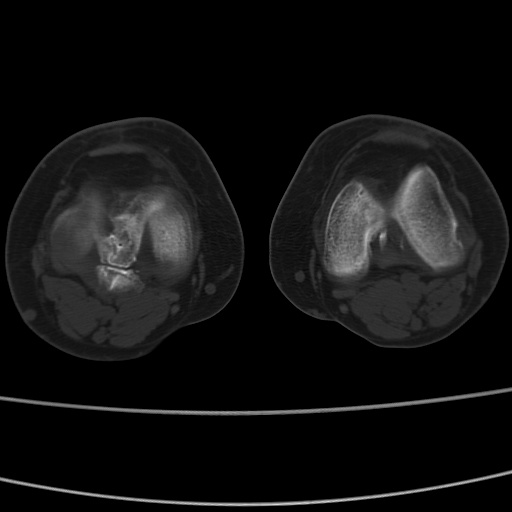

女性,50岁。【请提供患者临床症状体征】

右膝关节退行性改变,关节游离鼠。

右膝关节退行性改变,滑膜黏液囊钙/骨化并游离。

右膝关节退行性改变